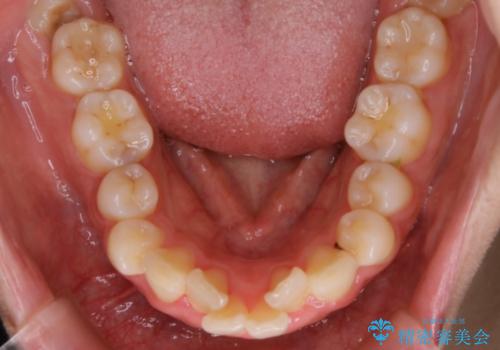

- 歯のガタつきと口元の突出感を主訴に来院されました。

装置の希望がインビザラインだったため、非抜歯でインビザラインの特徴を最大限に生かして行う矯正治療を選択しました。